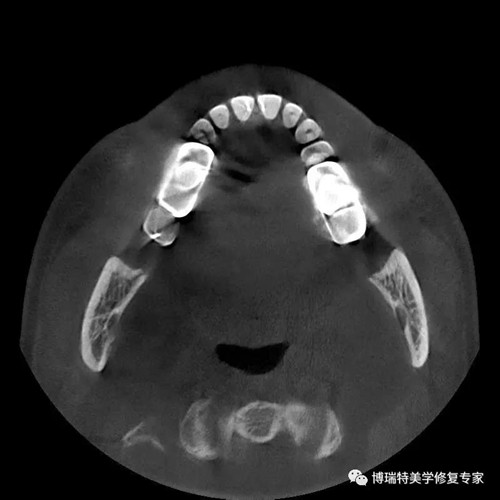

智能3D全景CBCT 多金属去伪影图

普通CBCT 多金属去伪影图(同一患者)

上颌窦底,骨小梁与下颌神经管清晰可见

植体周围无阴影,植体螺纹清晰可见